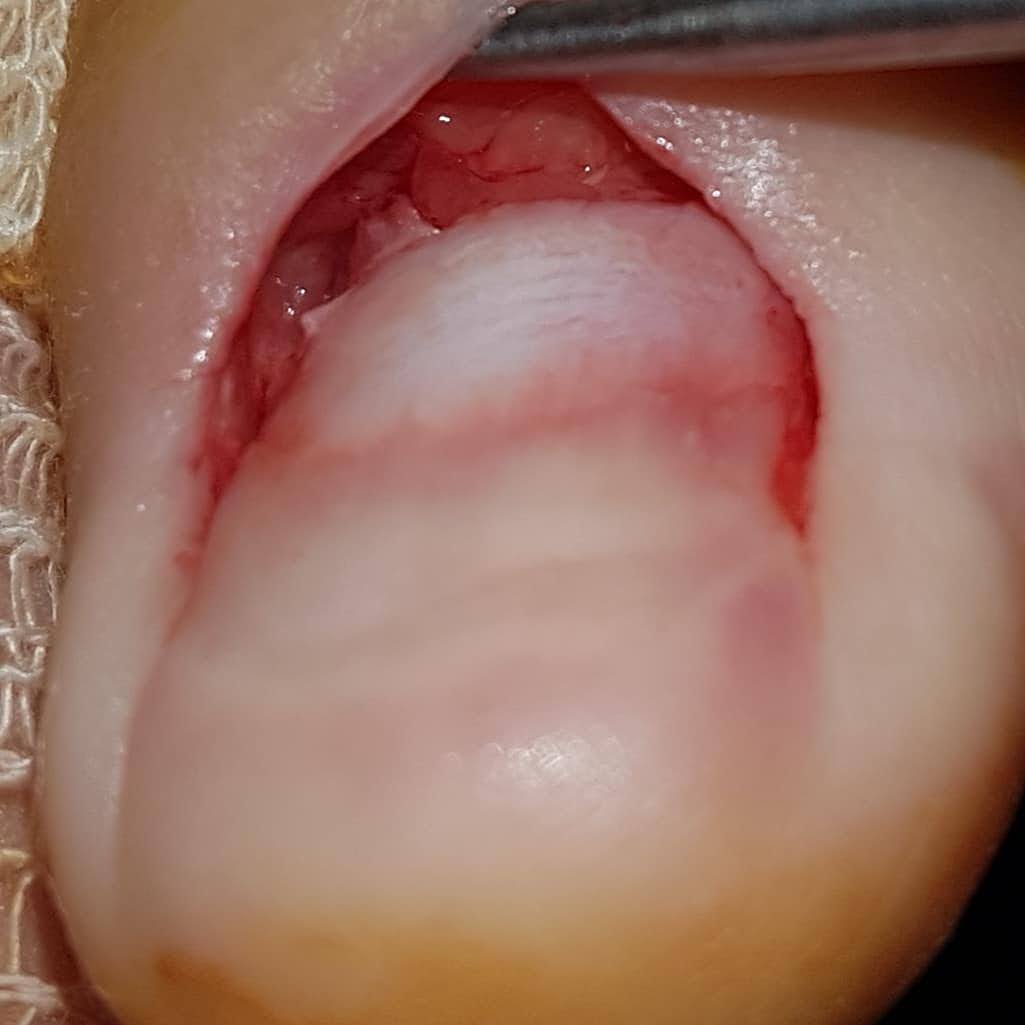

Paciente que refiere desde hace tres meses dolor en el canal peroneal de la uña del primer dedo. Comenta que le supura, le echa agüilla. Ha ido al médico en dos ocasiones y le han mandado antibióticos.

No parece hematoma y el dolor es intenso, no refiere trauma.

Le realizo exéresis parcial de la uña y aparece una tumoración subugueal que extirpo con el electrobisturí y remito a anatomía patológica.